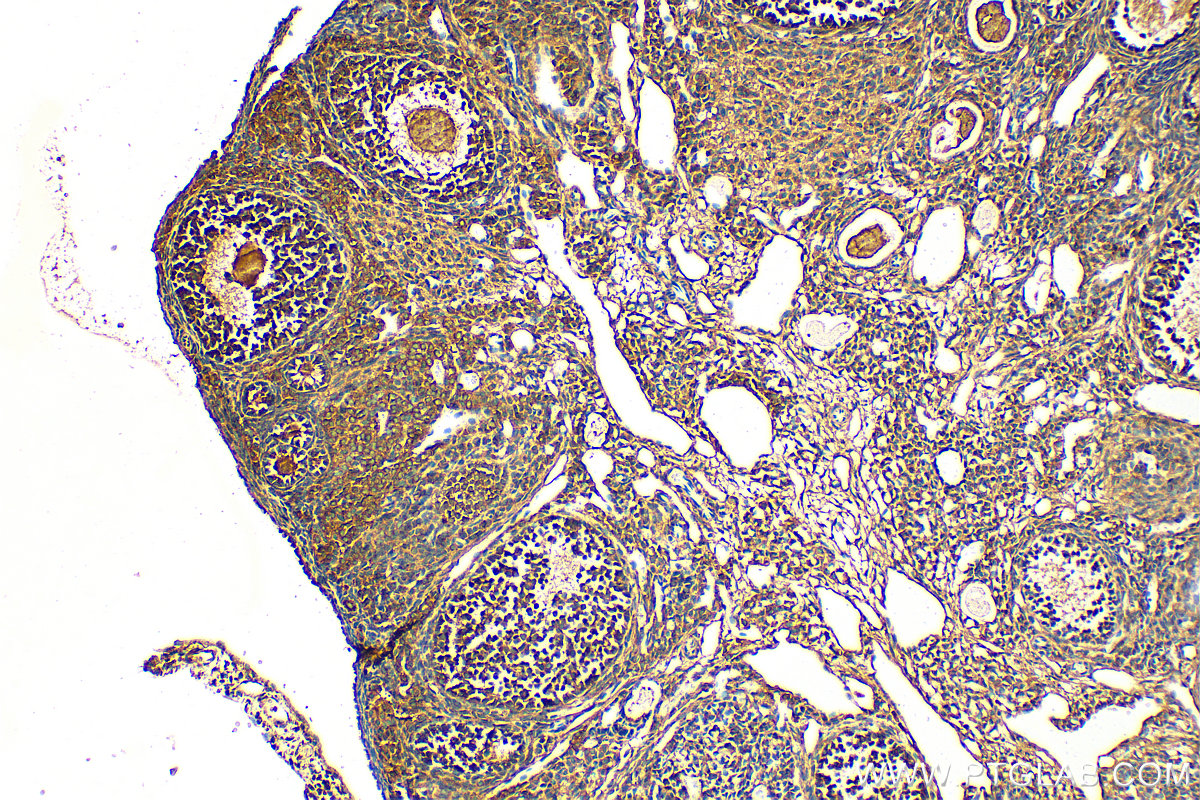

14007-1-AP targets ESR2 in WB, ChIP, ELISA applications and shows reactivity with human, mouse samples.

| 经测试应用 | WB, ELISA Application Description |

| 基因名称 | ESR2 |